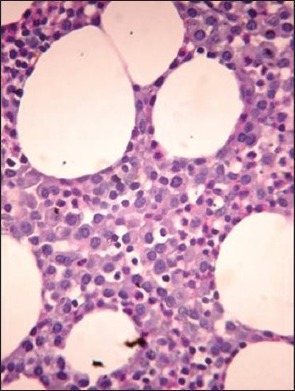

The clinicopathologic characteristics of all 14 patients with MM (13 newly diagnosed, 1 relapsed) are presented in Table 1. There were 11 males and 3 females with age range of 38-81 years (mean = 54 years, standard deviation = 10.7); and all were symptomatic at the time of evaluation. Eight (57%) were in Durie and Salmon Stage II, 5 (37%) Stage III and 1 (7%) in Stage I. Out of 14 cases, 10 (71.5%) presented with advanced lytic bone lesions, and two had organomegaly (one of which was de novo plasma cell leukemia). All, except one, had demonstrable light chain restriction (7 ‘ĸ’, 6 ‘λ’) by either IHC or biochemical assay techniques. Corrected serum calcium was found to be within normal range (≤11 mg/dL) in the majority of patients. On bone marrow evaluation, 10/14 (71%) cases showed an interstitial pattern of infiltration with or without focal nodularity; and 4 (29%) had packed marrow (diffuse pattern). Out of 14 cases, 10 (71%) cases were in Bartl's histologic Stage III (>50% tumor cells); and in 7 (50%), myeloma cells exhibited a high grade (blastic or pleomorphic) phenotype. Intracytoplasmic (Russell bodies) and intranuclear (Dutcher bodies) were noted in 11/13 patients; and in two intracytoplasmic crystalline inclusions were seen [Figures [Figures1a1a–g].

| Fig. 1e Periodic acid Schiff (PAS) stained bone marrow trephine sections showing a diffuse pattern of infiltration by myeloma cells (packed marrow) (×400)